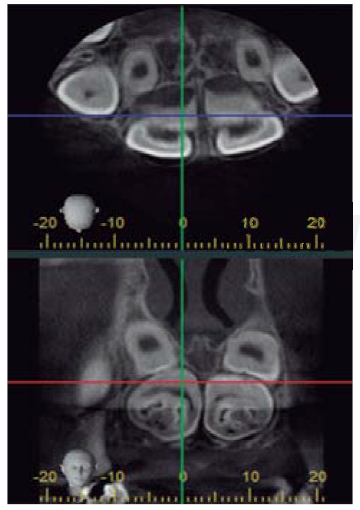

Se llevaron a cabo radiografías panorámicas, y un estudio imagenológico mediante tomografía axial computarizada, para la valoración del niño.

Radiográficamente, se observaron dos zonas radiopacas pericoronarias en región de órganos dentales 11, 12, 21, 22 y en ambas zonas de premolares mandibulares, rodeadas por un halo radiolúcido (Figura 2), se indicó como diagnóstico presuntivo odontomas compuestos y órganos dentarios supernumerarios respectivamente, para los cuales, se realizó anestesia local con carpules de lidocaína 2% (1:80,000) y abordaje quirúrgico con bisturí tipo Bard-Parker No 3, enucleación completa de las lesiones tumorales con pinza gubia, elevadores rectoapical, exodoncias de supernumerarios con elevadores angulados, síntesis con aguja y sutura no reabsorbible; para el postoperatorio, se prescribieron fármacos antiinflamatorios y remisión a la Especialidad de Ortodoncia y Ortopedia Maxilar, asimismo, fueron dadas recomendaciones a su madre; ulterior al mencionado procedimiento, el diagnóstico es sustituido por odontomas complejos, debido a sus características morfológicas y posterior examen histológico confirmatorio, además la corroboración de supernumerarios (Figuras 3 y 4). Microscópicamente, la lesión estaba constituida por una mezcla desordenada de tejidos dentarios, en los que se identificaba dentina, esmalte, tejido pulpar y cemento, así como algunos focos de células odontoblásticas. En las muestras (odontomas) analizadas no se evidenciaron características de malignidad.